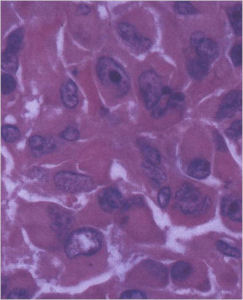

- They have a similar appearance microscopically as a conventional osteoblastoma except the osteoblasts are twice as large and have an epithelioid quality with abundant eosinophilic cytoplasm (Epithelioid Osteoblasts).

The differential between osteoid osteoma, conventional osteoblastoma and aggressive osteoblastoma is based on size and the presence of epithelioid osteoblasts. Can have epithelioid osteoblasts in osteoid osteoma and conventional osteoblastoma but they do not occur in cohesive sheets that fill intertrabecular spaces

Aggressive Osteoblastoma vs. Osteosarcoma

Osteosarcoma:

- Cellular atypia

- High mitotic rate

- Atypical mitotic figures

- Abundant lacelike osteoid

- Permeative growth into adjacent bone and soft tissue

- Presence of neoplastic cartilage

- No peripheral shell of reactive bone